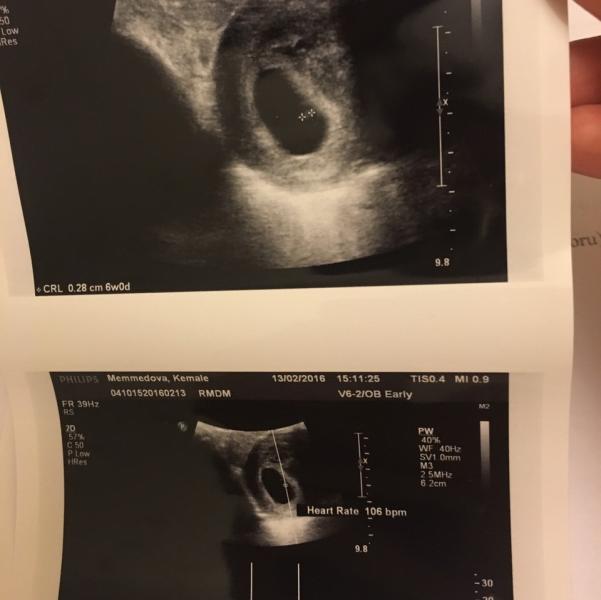

А вот и наша первая фотография 😍😍😍слава Богу, все нормально, нам 6недель! Есть гематома, но уже рассасывается, незначительные выделения были изза этого. Сердцебиение услышала, аж у самой дыхание перехватило и давление подскочило от волнения 😆узнала о вопросах , может кому интересно , насчёт эпиляции, сказал , живот бикини нельзя , остальное можно. Красить волосы тоже нельзя, шеллак И так далее проблем нет, кофе нельзя , только если давление упало, можно.